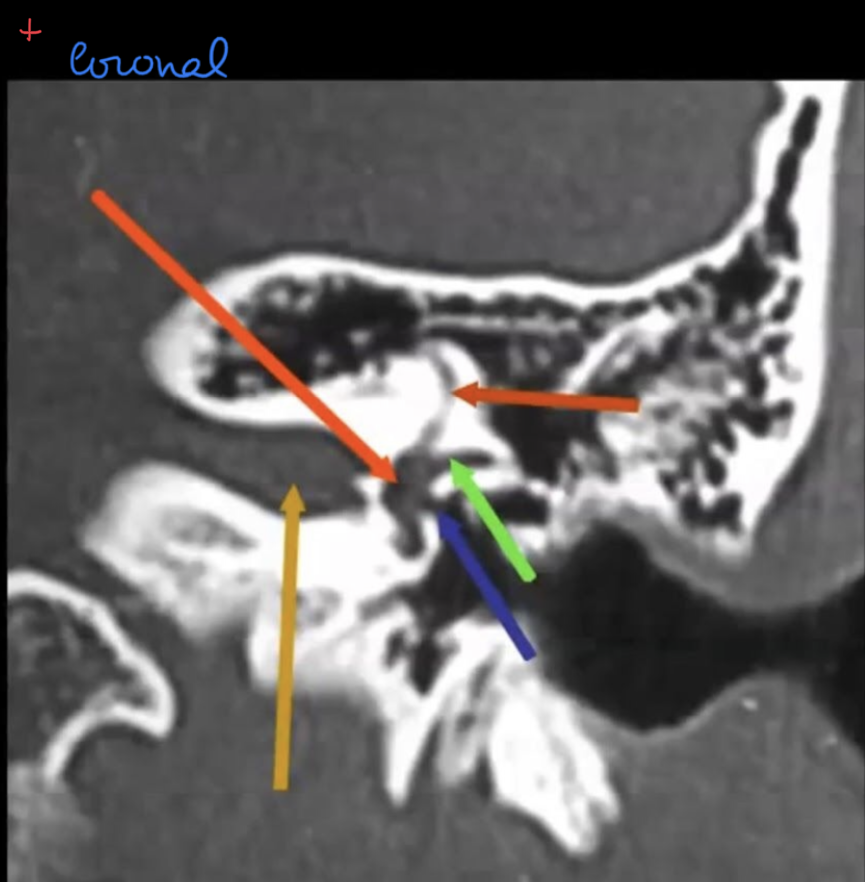

Tell the traject of the facial nerve in the skull base?

Nerves inside the IAC with subdivisions?

?